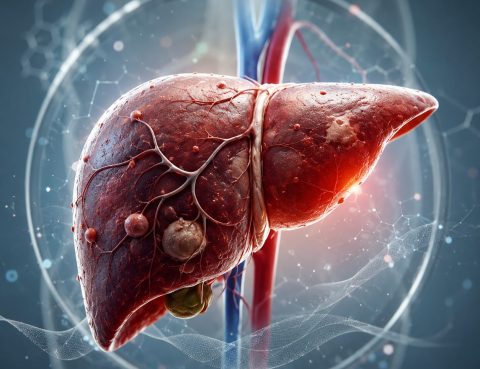

🩺 الكبد الدهني: مشكلة صحية صامتة لا يجب تجاهلها أصبح مرض الكبد الدهني من أكثر الحالات الصحية شيوعًا في السنوات الأخيرة، نتيجة العادات الغذائية غير الصحية 🍔، وقلة النشاط البدني 🛋️، وتغير نمط الحياة. ⚠️ ما هو الكبد الدهني؟ هو تراكم الدهون داخل خلايا الكبد بشكل زائد عن الطبيعي، مما قد يؤدي مع الوقت إلى…